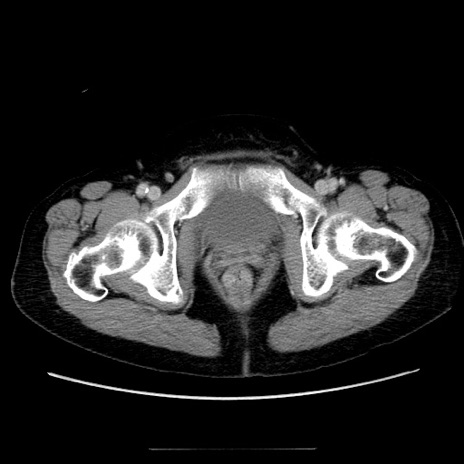

症例5(横断像)

【症例】70歳代女性

【主訴】お腹が張る

【現病歴】1週間くらい前から腹部膨満の自覚あり。昨日夜から増悪したため、本日救急外来受診。

【身体所見】意識清明、BT 36.5℃、BP 165/106mmHg、HR 80bpm、SpO2 98%、腹部:膨満、軟、自発痛・圧痛なし、触診にて不快感あり、腸蠕動音:減弱

【データ】WBC 12600、CRP 1.04